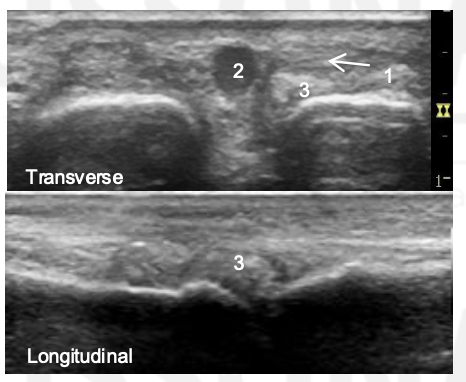

What is the arrow pointing to?

Synovial Distension

What is the abnormality?

1: Synovium, 2: Flexon Tendon, 3: Proximal Phalanx, 4: Middle Phalanx

1: Synonym, 2: Flexor Tendon; 3: Osteophyte

What is 3?

This is the interface sign in a normal MCP